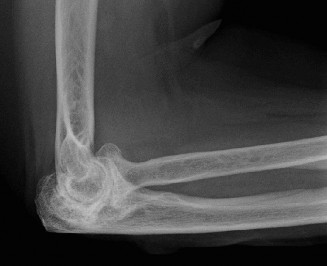

The correct answer is (C). Core decompression via insertion of pins into the area affected by AVN is thought to improve symptoms in patients with Ficat stage I or II by reducing bone marrow pressure and encouraging new vasculature to form. Patients are managed postoperatively in a sling for a few days and can perform shoulder range of motion as tolerated. Choice A would be more appropriate in a more advanced stage of AVN and/or if conservative treatment and core decompression have failed to relieve pain. Choices B and D are incorrect as they would be reserved for the elderly patient with advanced AVN characterized by concurrent osteoarthritic changes, with or without rotator cuff function. Objectives: Did you learn...? Understand the etiology of osteonecrosis of the humeral head? Recognize the clinical presentation of osteonecrosis of the humeral head? Manage a patient with osteonecrosis of the humeral head? CASE 20 Dr. Anna Cohen-Rosenblum A 72-year-old, right-hand-dominant male with a history of type 2 diabetes, hypertension, and coronary artery disease presents to clinic for a second opinion regarding worsening left shoulder pain 8 months after undergoing a left total shoulder arthroplasty. He had an uncomplicated procedure and has had no major postoperative complications thus far; however, he has never been completely pain free since his procedure. He denies any recent trauma, fevers, chills, or drainage from the incision site. On examination, the incision sites are clean, dry, and intact, and he has mild tenderness to palpation diffusely over the left shoulder as well as decreased range of motion. Imaging is shown in Figure 2–55.

Figure 2–55

What is the most appropriate next step in his management?

The correct answer is (C). This patient’s story of acutely worsening pain without known trauma and with a history of orthopaedic implants is suspicious for infection. Risk factors for infection include rheumatoid arthritis, diabetes mellitus, systemic lupus erythematosus, malignancy, immunosuppression, etc. The first step in this diagnosis would be CT arthrogram of the shoulder to evaluate for loosening as sign of infection. A is incorrect as, although infection is on the differential, it has not yet definitively been diagnosed and therefore an immediate irrigation and debridement would not be indicated. MRI (Choice B) might be helpful in identifying a joint effusion or bony edema/signal intensity but would not provide as useful information as synovial fluid would at this point. Choice D is incorrect because the patient must be worked up for infection before deciding on conservative

CT arthrograms of the patient’s left shoulder are shown in Figure 2–56. CRP is <3, ESR 45. The patient continues to have pain, so you decide to perform arthroscopic biopsy to obtain tissue cultures. Frozen sections show <5 PMNs per hpf, and Gram stains are all negative.

Figure 2–56

The correct answer is (B). Figure shows contrast under the glenoid component. Given the patient’s normal inflammatory markers and frozen sections combined with continued pain and loosening on CT, infection with P. acnes(an organism that is very difficult to isolate) should be investigated by holding any cultures for at least 2 weeks to see if it will eventually grow. Chocolate agar (Choice C) is mainly used for growing species such as H. influenzae and Neisseria meningitidis not P. acnes. A is incorrect since the patient’s cell count and frozen sections are clearly abnormal, therefore referral to pain clinic would not be appropriate. However, Choice D would be too aggressive an approach given that no organisms have been isolated, frozen sections show <5 PMNs per hpf, and the patient has relatively normal inflammatory markers.